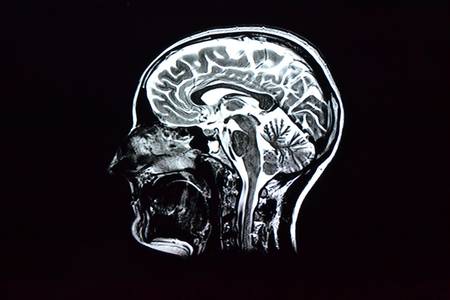

Наконец, получен ответ на считавшийся всегда риторическим вопрос: где у человека совесть? Она находится в боковой фронтальной коре головного мозга, т.е. прямо над бровями.

Область мозга, которая не позволяет нам принимать плохие решения, оксфордские ученые открыли при помощи сканирования мозга 25 мужчин и женщин. Затем они сравнили снимки мозга добровольцев со снимками макак, которые являются одними из ближайших наших родственников. Боковая фронтальная кора состоит из 12 отделов. 11 из них одинаковые и у людей, и у обезьян, а вот 12-й, боковой лобный полюс, у животных отсутствует.

Грубо говоря, совесть является маленьким сгустком нервной ткани в форме шарика и располагается в боковой фронтальной коре мозга.

Эта часть головного мозга особенно важна в многозадачной деятельности. Например, если человек решит что-то сделать, то она будет размышлять о других вариантах и представлять их последствия. Из статьи в журнале Neuron, где оксфордские ученые опубликовали результаты своего исследования, следует, что эта часть мозга также позволяет нам учиться на чужих ошибках, ускоряет приобретение новых навыков и умений и имеет еще много полезных функций. Одна из них - выбор между добром и злом.